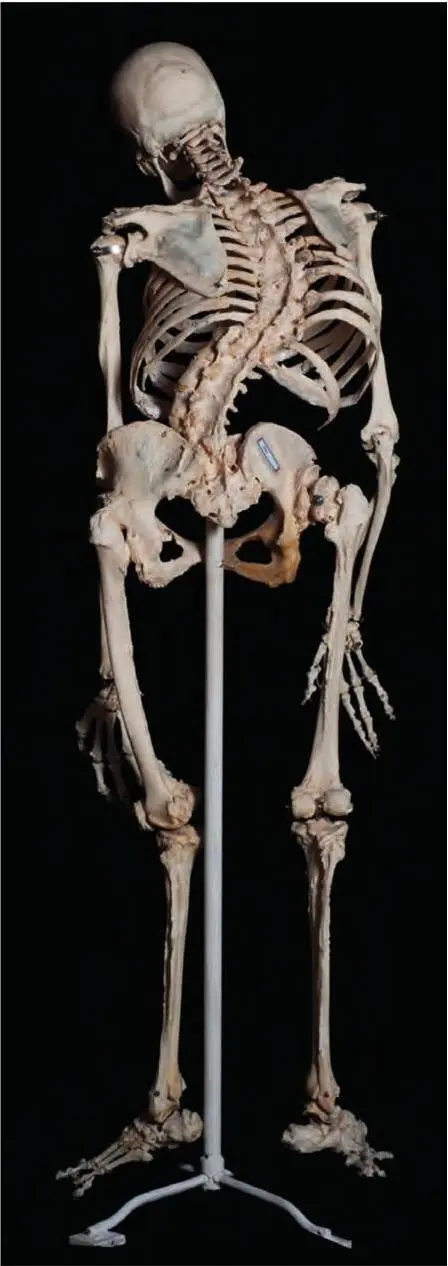

Рис. 41. Скелет человека с выраженным кифосколиозом (патологические изгибы) и тотальным срастанием (синостозированием) позвонков.Анкилоз (обездвиживание) левого тазобедренного сустава. Натуральный анатомический препарат

По данным статистики, уровень общей патологии суставов в 2012 г. превысил 11,35 млн человек (или 77 случаев заболевания на 1000 жителей России), что на 35 % выше, чем 10 лет назад.